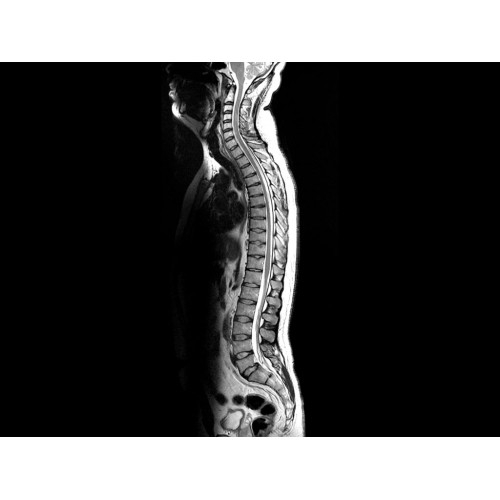

• Визуализация всего позвоночника слиянием двух участков — получить изображение всего позвоночника можно намного быстрее.

• Магнит переработанной конструкции — полностью новый магнит длиной 145 см обеспечивает однородную контрастность тканей в удобных для пациента условиях.

МР-томограф Optima MR450w с диаметром туннеля 70 см обеспечивает более комфортные условия для пациентов, в первую очередь, для полных людей, детей и лиц, страдающих клаустрофобией. При этом повышенное удобство для пациентов обеспечено не только нешироким туннелем — клинические приложения нового поколения сокращают продолжительность исследований, а улучшенный поток воздуха обеспечивает удобный микроклимат во время исследования.